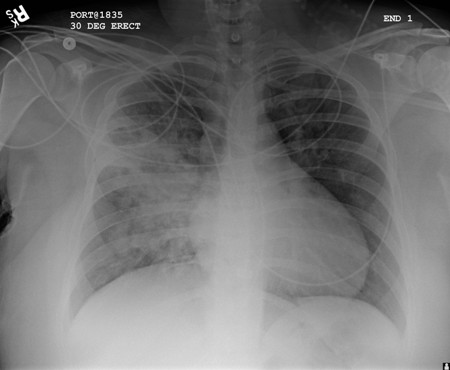

Pneumonia por aspiração

Opacificação aumentada da região peri-hilar direita e do segmento superior dos lobos inferior e superior direitos, compatível com agravamento da pneumonia por aspiração